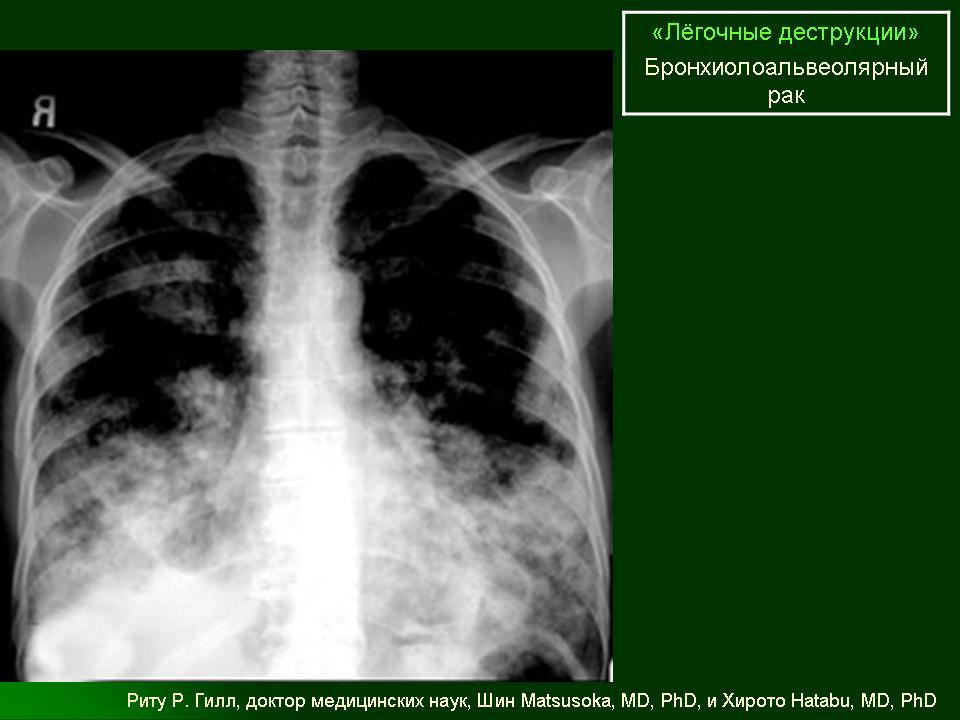

ОГК. Легочные деструкции (кавитации). +

Легочные деструкции (кавитации)

Легочные кавитации. Радиопедия.